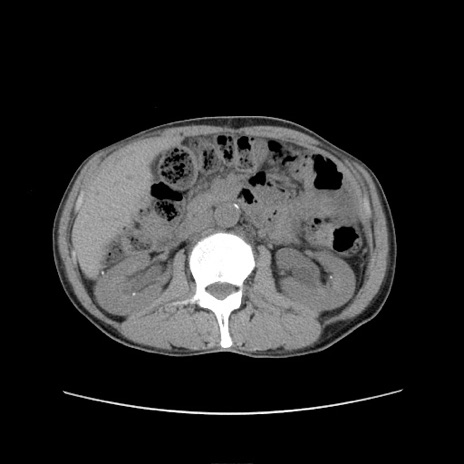

症例11(横断像)

【症例】 60歳代男性

【主訴】 下腹部痛

【現病歴】 本日夜中より下腹部痛の症状認め、受診。

【既往歴】 膀胱癌(膀胱全摘+尿管皮膚瘻術) 、胃癌術後

【身体所見】 BT 35.3℃、PR 58/min、BP 136/98mHg、腹部平坦、軟、腸蠕動音±、ストマ留置あり、左上腹部~正中部に圧痛あり、反跳痛なし。

【データ】WBC 5100、CRP0.01